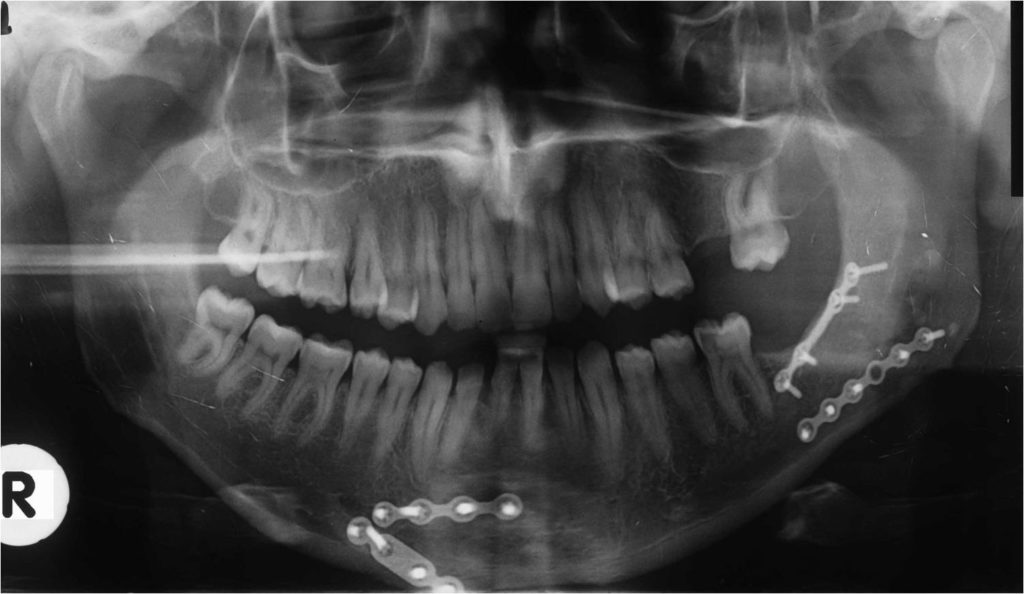

Στοματικό & Γναθοπροσωπικό Τραύμα